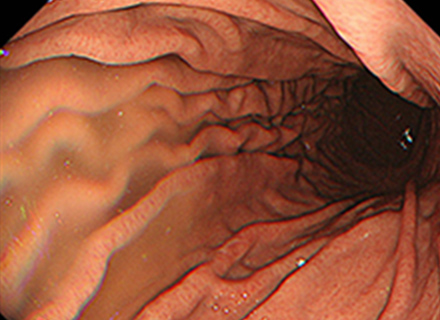

下部消化管(大腸カメラ)内視鏡検査では、肛門より太さ約13~14mmの内視鏡スコープを挿入し、空気(炭酸ガス)の注入を行いながら大腸のヒダをたぐり寄せて盲腸まで挿入します。 盲腸へ到達後、ポリープやがん、炎症などの病気がないか観察しながら内視鏡スコープを抜いてきます。 途中で病変が見つかった場合は、必要に応じて病変の一部を採取(生検)して調べたり、ポリープや早期がんなどの病変を内視鏡的に切除することもできます。検査時間は通常10~15分程度ですが、ポリープを切除すると通常より時間は長くかかります。